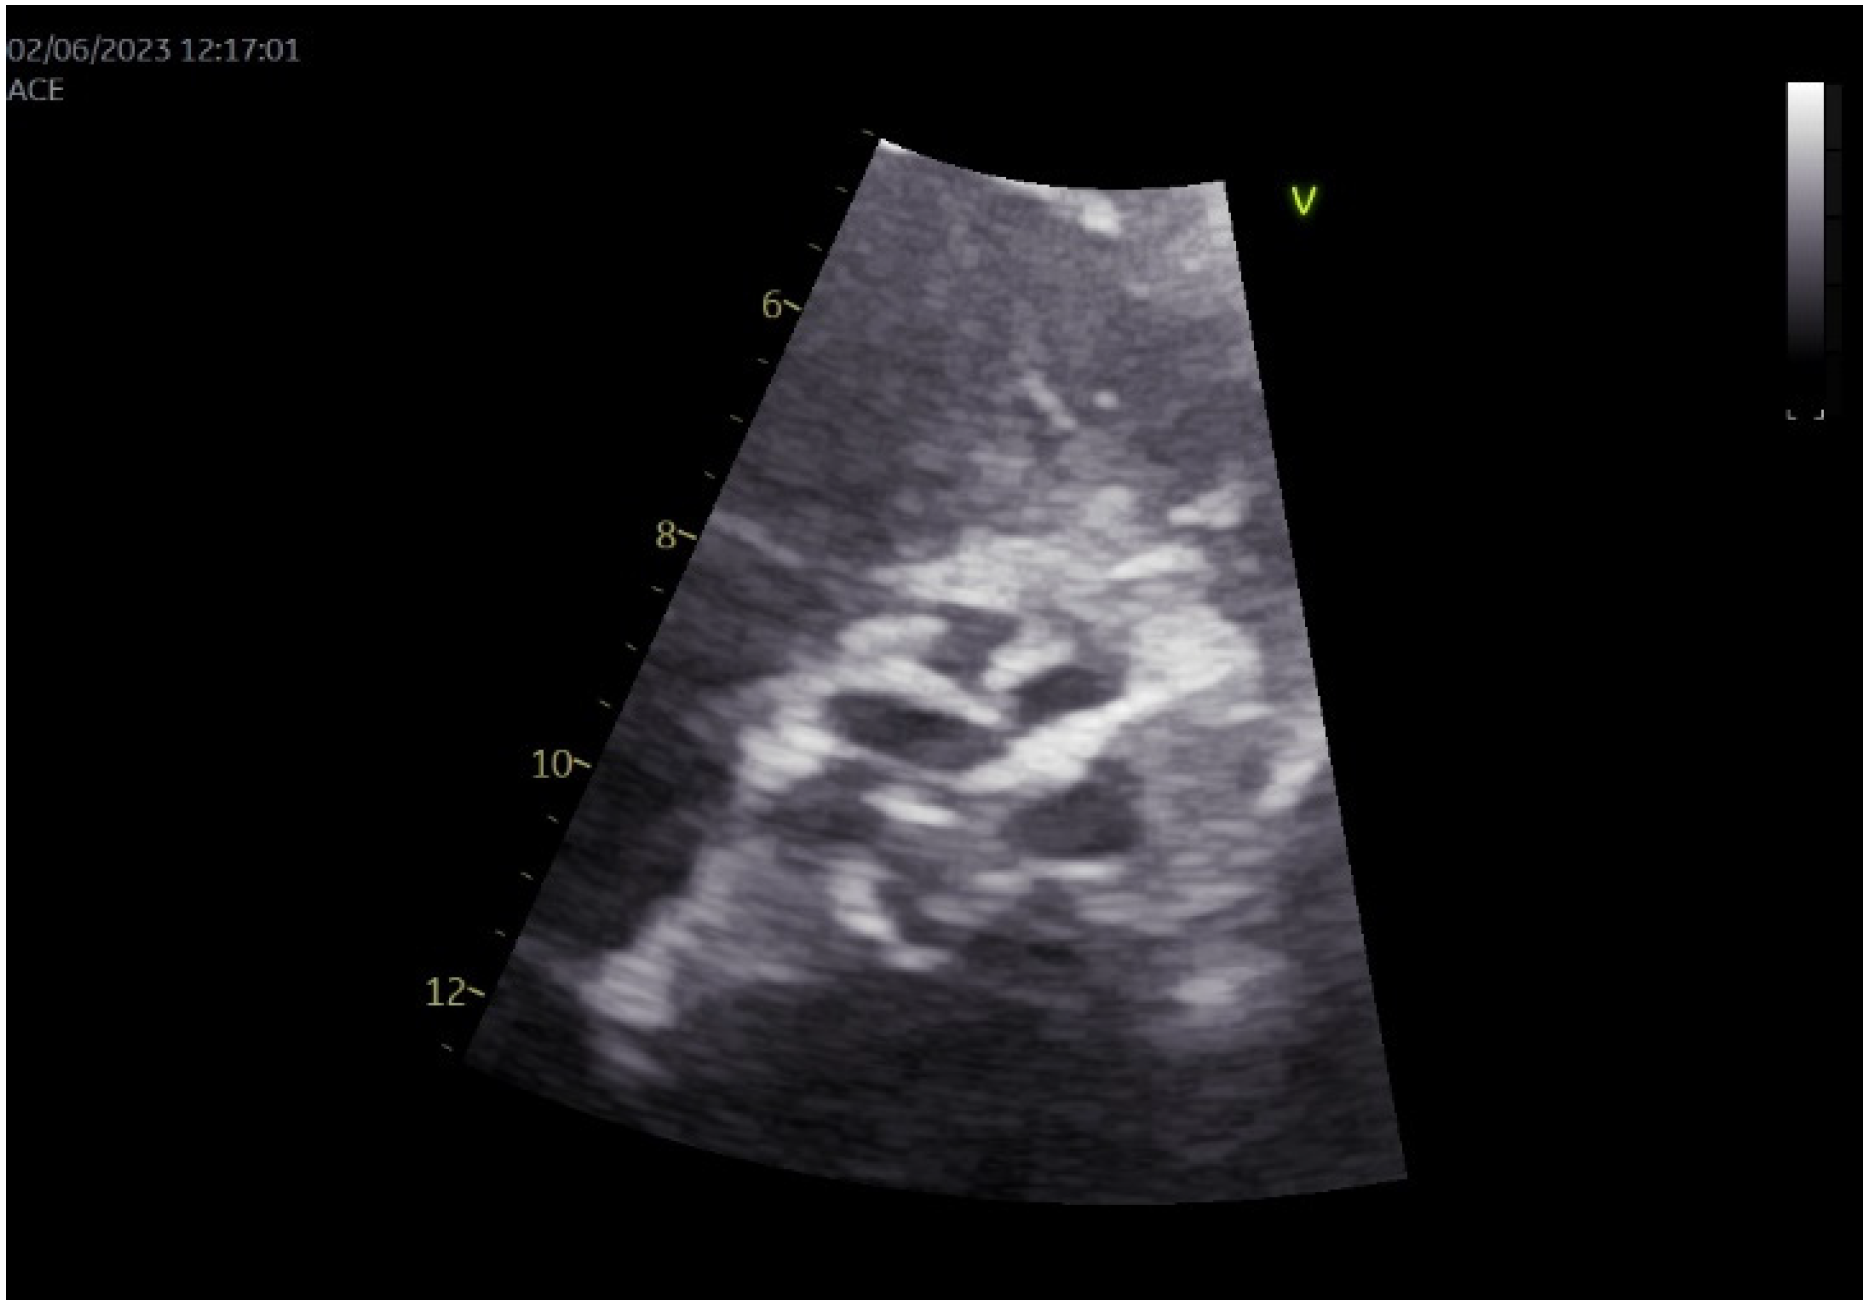

2. Case Presentation